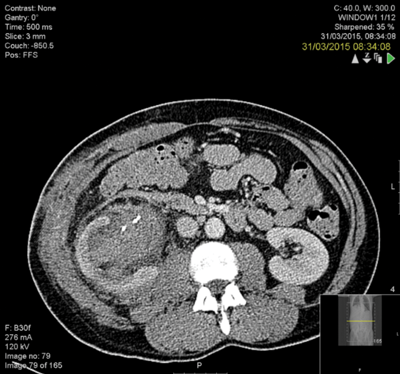

A 76-year-old male with end stage renal failure due to obstructive uropathy from benign prostatic enlargement was transferred from a referring hospital. A right ureteric stent had been placed and a left sided stent was sited too far proximally in the ureter (Figure 1). Comorbidity included ischaemic heart disease, cardiac failure and the patient was anti-coagulated. There had been one failed attempt to re-position the stent.

Figure 1.